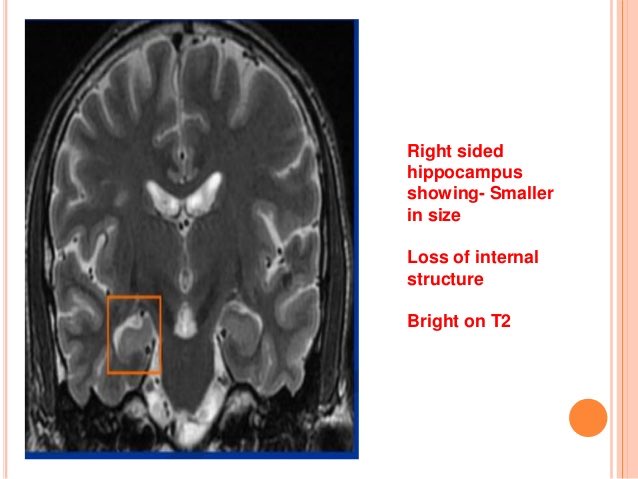

٦/التقييم في الدراسة اعتمد على قياس أمور بنيوية منها ضمور الحصين (hippocampal atrophy)، المادة الرمادية، المادة البيضاء واخرى معرفية.

٩/النتائج: كل ما زادت جرعة استهلاك الكحول زاد ضمور الحصين في الدماغ (وهذا يرتبط بضعف مهارات التعرف على المواقع، ضعف الذاكرة، والنسيان).

١١/حتى من يشربون الكحول باعتدال (١٤-٢١ وحدة اسبوعياً) الخطر اعلى بثلاث مرات في ضمور الجزء الأيمن من الحصين (right sided hippocampal atrophy)